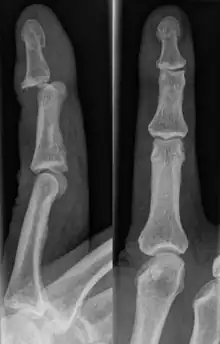

A jammed finger can generally be diagnosed via physical examination. The relative position of the bones of the finger give an indication as to potential dislocations or fractures.[3] However, it is recommended to seek medical attention regardless of whether or not a dislocation or fracture is evident.[6] This is because untreated jammed fingers can lead to future pain and stiffness, with joint surface fractures increasing the risk of arthritis.[6] The areas around the injury may be palpated in order to ascertain the areas of maximum pain.[2] If the injury is a joint injury (namely a sprain or dislocation), the point of maximum pain will be close to the joint rather than mid-phalanx (mid-bone).[2] Due to the risk of dislocations or fractures, stability testing is not recommended until after an x-ray has been conducted and the presence of a dislocation or fracture has been confirmed or rejected.[2] In extremely painful cases, a digital nerve block, where anaesthetic is injected in the web to either side of the affected finger, may be employed to enable assessment of the injury.[2] X-rays may be employed to achieve a more accurate diagnosis of a jammed finger, enabling the identification of varying types of dislocation or fractures. In order to account for all possibilities, it is recommended that a variety of views (lateral, oblique, and anteroposterior) are observed.[2]

Dislocations can be categorised based on location and type. The finger can be split into three bones and two joints in an alternating order. From the fingertip to the knuckle, these are as follows; distal phalanx, distal inter-phalangeal (DIP) joint, middle phalanx, proximal inter-phalangeal (PIP) joint, and proximal phalanx. DIP dislocations are much less common than PIP dislocations,[2] due to the "stability provided by strong collateral ligaments, palmar plates, and tendinous insertions, as well as the short lever arm of the distal phalanx".[7] Dislocations can be categorised based on the direction that the fingertip moves in relation to the knuckle, be it in the direction of the palm (volar dislocation), or the direction of the back of the hand (dorsal dislocation). Of the two, dorsal dislocations are more common.[3] If reduction has been attempted, an x-ray of the dislocation should appear concentric if successful.[2] However, if there is a fracture present, there will be a misalignment of the joint, which will be evident from the radiograph.[2] Bach suggests a referral to a hand surgeon if a misalignment is present.[2]

Fractures are instances where the bone's structural integrity has been compromised. This is indicated by midshaft pain, as well as visual midshaft angulation or rotation.[3] As with any skeletal injury, an x-ray can be conducted to verify the presence of a fracture.[1] The distal phalanx is especially vulnerable to avulsion fractures, where a fragment of bone is ripped off when the tendon separates from the phalanx.[1] Avulsion fractures are especially common following a first time dislocation.[1] These are especially concerning, as it may indicate a complete tear of the extensor digitorum tendon. If left untreated, this may lead to permanent DIP extensor lag (inability to fully straighten the finger).[8]